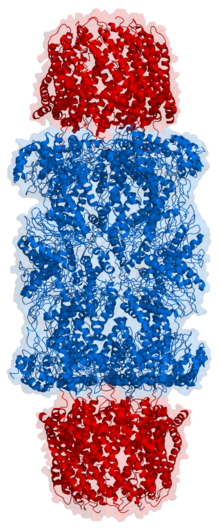

Der Begriff Proteasom bezeichnet im Allgemeinen einen Proteinkomplex, der in Archaeen und einigen Bakterien vorkommt und bei Eukaryoten sowohl im Zellkern als auch im Zytoplasma vorliegt. Im Speziellen unterscheiden sich Proteasome in ihrer Zusammensetzung zwischen verschiedenen Taxa. In Säugetieren liegen Proteasome auch innerhalb eines Organismus in verschiedenen Formen vor, z. B. als freies 20S Proteasom oder in Kombination mit einem oder mehreren regulatorischen Partikeln (z. B. als 26S Proteasom). Proteasome spielen eine essenzielle Rolle für den kontrollierten Abbau von Proteinen in der Zelle und sind damit integraler Bestandteil der Proteinqualitätskontrolle in Zellen. Zum Abbau werden bestimmte Proteine entfaltet, in das Proteasom eingeschleust und dort von den katalytisch aktiven Untereinheiten des Proteasoms in kürzere Peptide geschnitten. Es handelt sich bei Proteasomen daher um multikatalytische Proteasen.

Das eukaryotische Proteasom besteht aus dem 20S Kern-Partikel, in dem die katalytischen Proteaseaktivitäten lokalisiert sind, und ggf. weiteren regulatorischen Proteinkomplexen, die an eines oder beide Enden des 20S Proteasoms gebunden sein können. Von besonderer Bedeutung ist der 19S Regulator (auch PA700), der eine zentrale Rolle beim Abbau ubiquitinierter Proteinsubstrate einnimmt. 20S Proteasome in Kombination mit einem oder zwei 19S Regulatoren werden als 26S Proteasom bezeichnet. Die weitere Unterscheidung zwischen 26S (20S + 1 x 19S) und 30S (20S + 2 x 19S) ist in der Literatur uneinheitlich. Neben dem 19S Regulator gibt es weitere Regulatoren wie z. B. den 11S Regulator (PA28αβ oder PA28γ) oder den im Zellkern lokalisierten Regulator PA200[1]. Proteasome können auch aus dem 20S Proteasom mit zwei verschiedenen Regulatoren bestehen, z. B. einem 19S Regulator an einem Ende und einem PA28αβ Regulator am anderen Ende. Diese Strukturen werden als Hybrid-Proteasome bezeichnet. Das 20S Proteasom formt eine zylindrische Struktur aus vier Ringen zu je sieben Untereinheiten. In der Mitte der beiden α-Ringe befindet sich eine Pore (englisch: gate), die den Eintritt von Substraten ins 20S Proteasom reguliert. Die Größe der Öffnung wird vorrangig vom gebundenen Regulator-Komplex reguliert. Die „Gate-Opening“ Funktion des Regulators wurde zuerst für 20S Proteasome der Hefe in Kombination mit PA26 Regulatoren aus dem Protozoon Trypanosoma brucei beschrieben[2]. Zudem wurde auch eine allosterische Regulation zwischen den katalytisch aktiven Untereinheiten des 20S Proteasoms und der α-Ring-Öffnung beschrieben[3].

Das 20S Proteasom hat die Form eines Zylinders und wirkt als multikatalytische Protease. Es besteht aus vier Ringen, die ihrerseits aus jeweils 7 verschiedenen Untereinheiten zusammengesetzt sind. Die äußeren Ringe bestehen aus α-Untereinheiten (α1-α7). Im Unterschied zu bakteriellen und Archeae-Proteasomen, die mehrere identische katalytische Untereinheiten besitzen, bestehen die inneren zwei Ringe der eukaryotischen Proteasome aus je sieben β-Untereinheiten, von denen jeweils drei Untereinheiten katalytisch aktive Proteasen darstellen (β1, β2 und β5). In der Mitte des 20S Proteasoms wird somit strukturell eine innere Kammer geformt, in der die Spaltung der Substrate abläuft. Zwischen den α- und den β-Ringen ergibt sich strukturell je eine weitere Kammer (Antechamber). Die katalytisch aktiven Untereinheiten kommen bei vielen Wirbeltieren in je zwei (für β1 und β2) oder drei (für β5) verschiedenen Varianten vor und die Zusammensetzung des 20S Proteasoms aus den jeweiligen Varianten bestimmt die Unterscheidung des Proteasoms als Standardproteasom (auch „konstitutives Proteasom“ genannt), Immunproteasom oder Thymoproteasom. In Standardproteasomen werden die Untereinheiten β1, β2 und β5 als Standardproteasom-Untereinheiten (auch konstitutive Untereinheiten) bezeichnet. Jede dieser drei Untereinheiten hat eine etwas andere proteolytische Aktivität: β1 spaltet die Peptidkette des entfalteten Proteins nach sauren Aminosäuren (Caspase-ähnliche Aktivität), β2 spaltet nach basischen Aminosäuren (Trypsin-ähnliche Aktivität) und β5 spaltet nach hydrophoben Aminosäuren (Chymotrypsin-ähnliche Aktivität). Die Struktur des 20S Proteasoms konnte mit hoher Auflösung durch Röntgen-Struktur-Analyse bestimmt werden[5].

Die 19S Komplexe sitzen bei Eukaryoten ähnlich einer Haube (cap) auf einer Öffnung oder beiden Öffnungen des 20S Komplexes. Sie regulieren den Zugang von Substraten zum 20S Komplex, indem sie Substratproteine entfalten und die Größe der α-Ring-Pore im 20S Komplex regulieren. Der 19S Regulator besteht aus Rpn- und Rpt-Proteinen. Die verschiedenen Rpn Untereinheiten (regulatory particle non-ATPases) sind zuständig für die Bindung von ubiquitinierten Substraten an den Proteasom-Komplex. Sie regulieren die Entfaltung des zum Abbau bestimmten Proteins, rekrutieren andere Faktoren ans Proteasom (z. B. das de-ubiquitinierende Enzym USP14) oder sind selbst an der De-Ubiquitinierung beteiligt (Rpn11)[6]. Am Transfer des Substratproteins in das 20S Proteasom sind die sechs Rpt-Untereinheiten (regulatory particle ATPasen) maßgeblich beteiligt. In Abhängigkeit von Adenosintriphosphat (ATP) und der Hydrolyse von ATP zu ADP durchläuft der Rpt-Ring einen komplexen Komformationszyklus, durch den die Substrate zum Abbau ins 20S Proteasom transloziert werden. Die Struktur des 19S Regulators konnte aufgrund seiner Dynamik erst durch die Entwicklung der Kryo-Elektronenmikroskopie in jüngerer Zeit näher aufgeklärt werden[7][8].